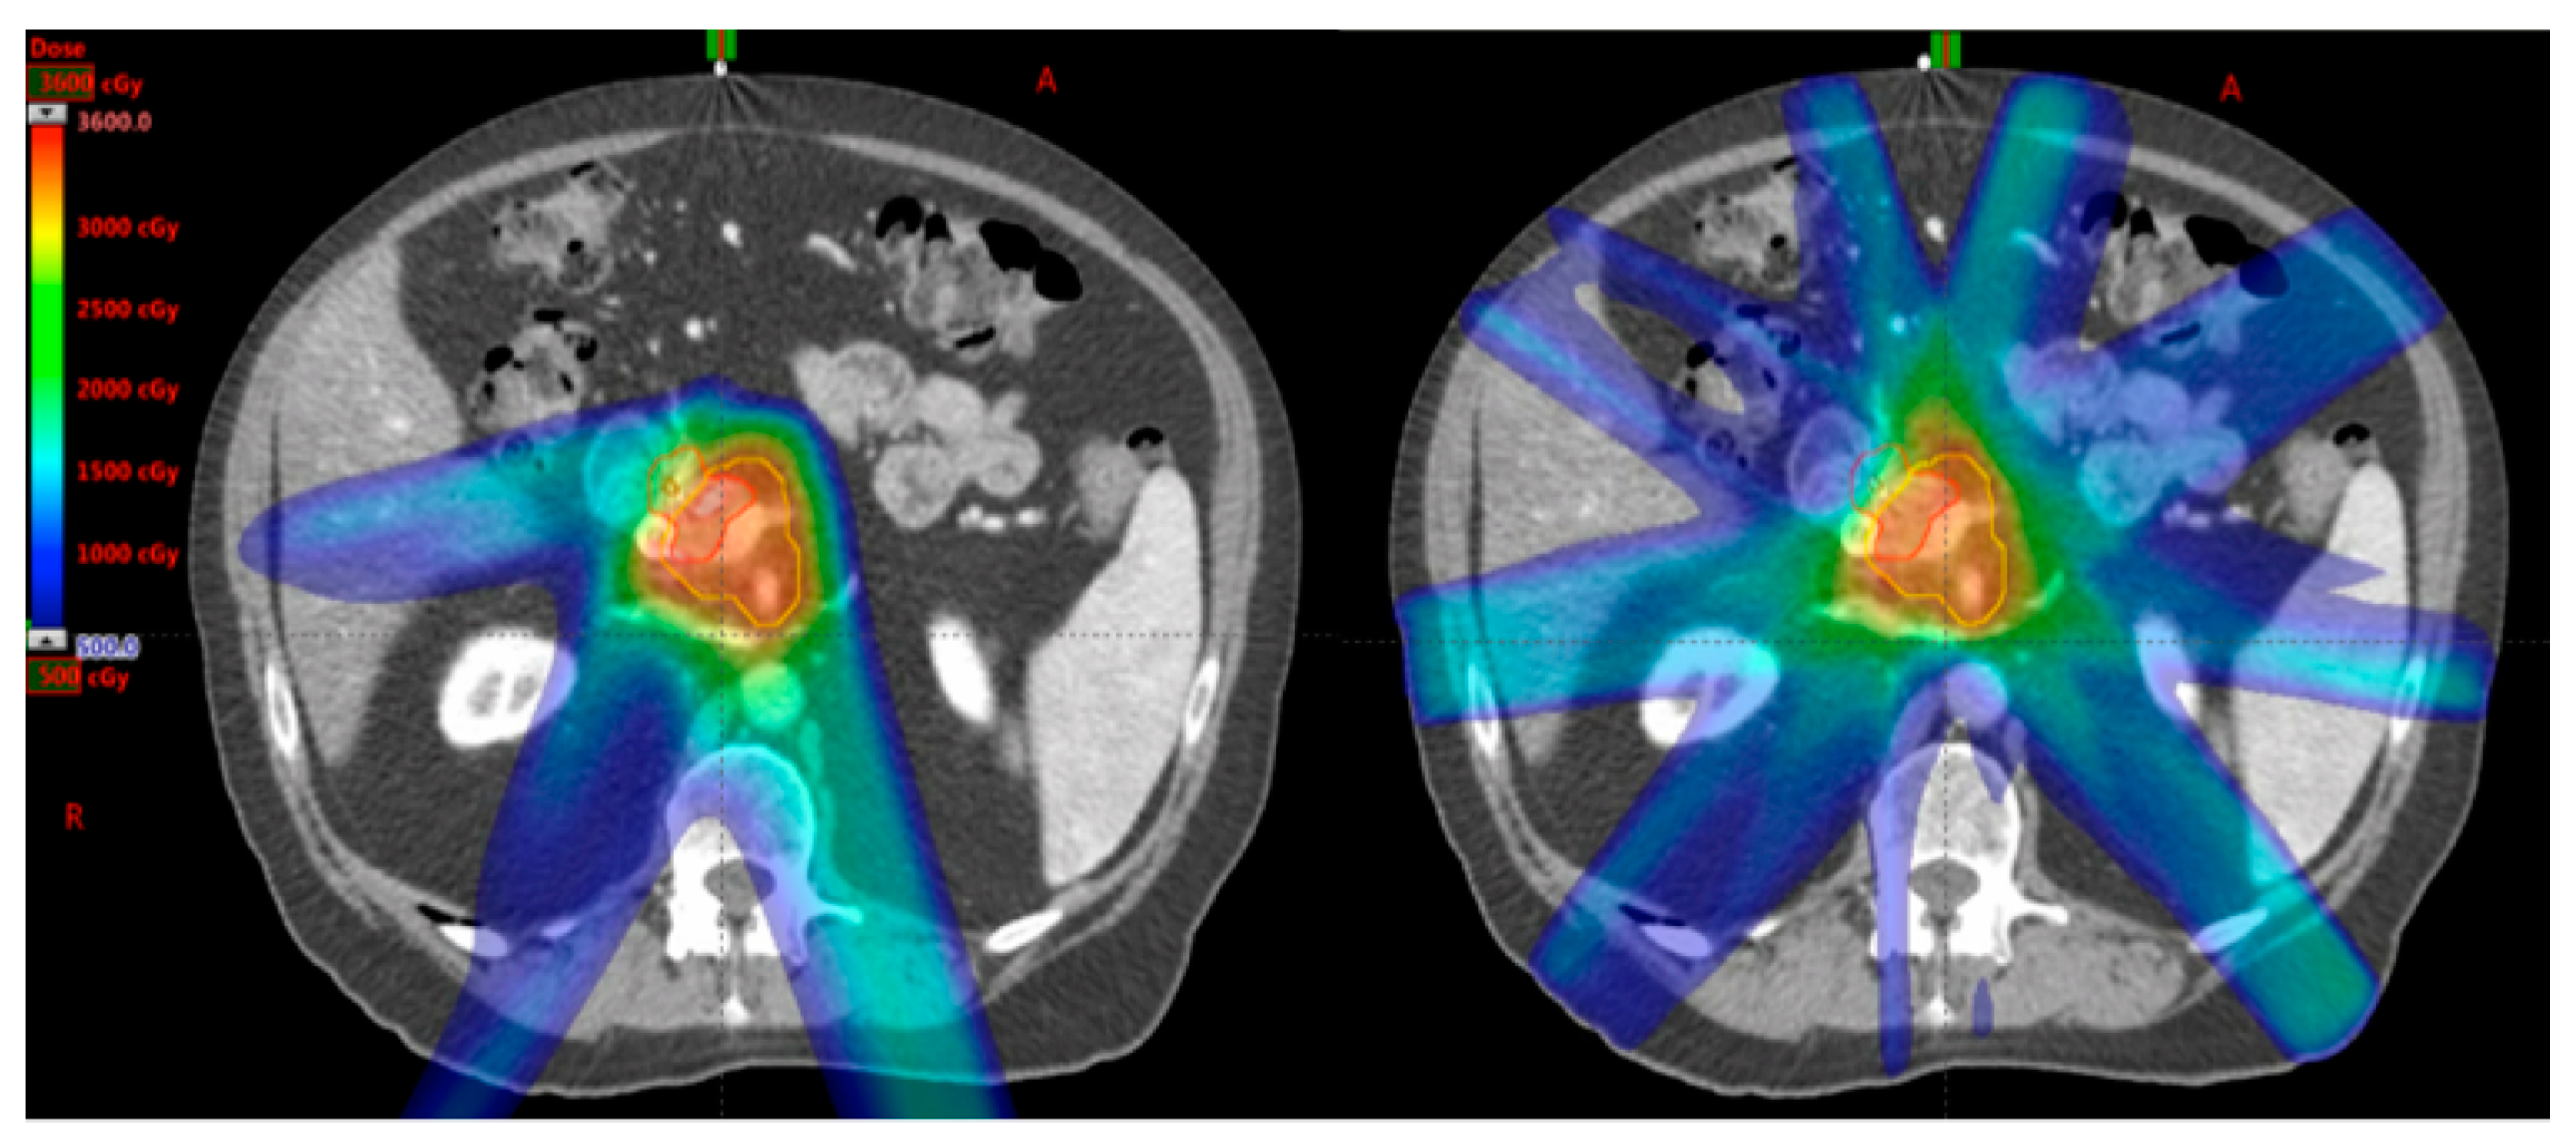

The proton beam, a particle therapy, has the benefit of delivering dose to the target with no exit dose in the beam path (Figure 2); thereby potentially reducing dose to the normal tissues within the exit beam path [25]. This, theoretically, may reduce both acute and late toxicities of treatment. In addition, with minimal dose in the exit beam path, proton therapy opens the door to possible dose escalation studies. As proton therapy is a relatively new player in the clinical radiation oncology domain, the evidence for the use in pancreatic cancer remains limited. Table 3 summarizes the current literature for particle therapy in pancreatic cancer.

Figure 2.

An example of proton (Left) and photon (Right) SBRT plans on the same patient. Note that there is less low dose scatter in the proton plan due to the inherent physical properties of proton particles compared to photon.